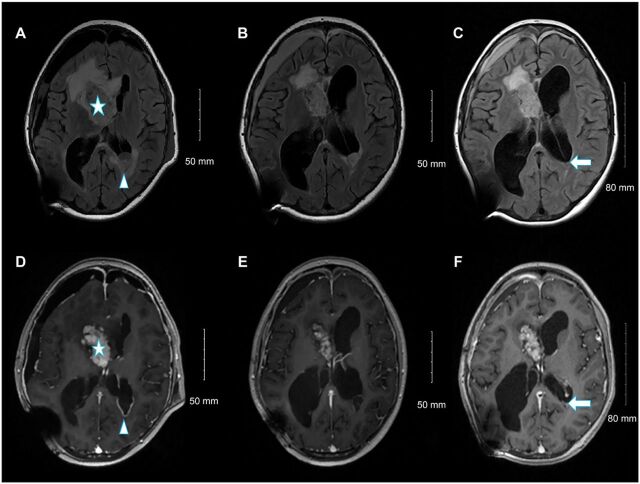

脐下巨细胞星形细胞瘤(SEGA)是一种罕见的环形星形胶质瘤,约占结节性硬化症(TSC)病例的25%。在此,我们将讨论 SEGA 的一种非典型表现,包括遗传改变、对临床表现的影响以及每种药物和手术治疗方案的决定因素。一名14岁的女孩因间歇性头痛和右侧脑室内肿块(起源于门罗孔附近)而就诊。由于肿瘤靠近重要结构,必须进行最大限度的安全切除,这才改善了她的症状。组织学检查结果显示她患有SEGA,基因测序显示她有TSC2基因突变。然而,完整的临床和放射学评估未能发现 TSC。两个月后,偶然发现了一个新的蝶鞍下结节。她的左枕角病变复发,弥漫性平滑脑膜强化,无脊柱下垂转移。由于肿瘤无法切除,她接受了依维莫司治疗。随后的影像学检查显示,残留病灶和新发病灶均有所减少。

Subependymal giant cell astrocytoma (SEGA) is a rare circumscribed astrocytic glioma that occurs in approximately 25% of all tuberous sclerosis (TSC) cases. Herein, we discuss an atypical presentation of SEGA, including the genetic alterations, impact on clinical presentation, and the determinants of each medical and surgical treatment option. A 14-year-old girl presented with intermittent headache and a right intraventricular mass originating near the foramen of Monro. The tumor's proximity to critical structures necessitated maximum safe resection, which improved her symptoms. Histological findings indicated SEGA, and genetic sequencing revealed a TSC2 mutation. However, complete clinical and radiological evaluations failed to reveal TSC. Two months later, a new subependymal nodule was incidentally found. She had a recurrent left occipital horn lesion and diffuse smooth leptomeningeal enhancement with no spine drop metastases. She was administered everolimus as the tumor was considered unresectable. Subsequent imaging revealed a reduction in both residual and new lesions.